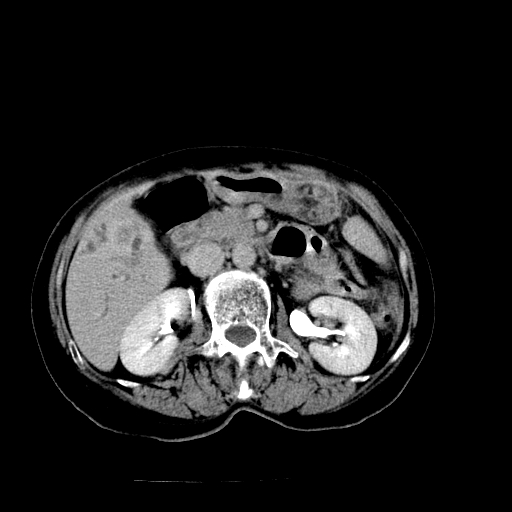

以下是引用随光逐影在2009-4-7 8:21:00的发言:[br]肝内外胆管多发性结石并肝内外胆管扩张;胆系感染。